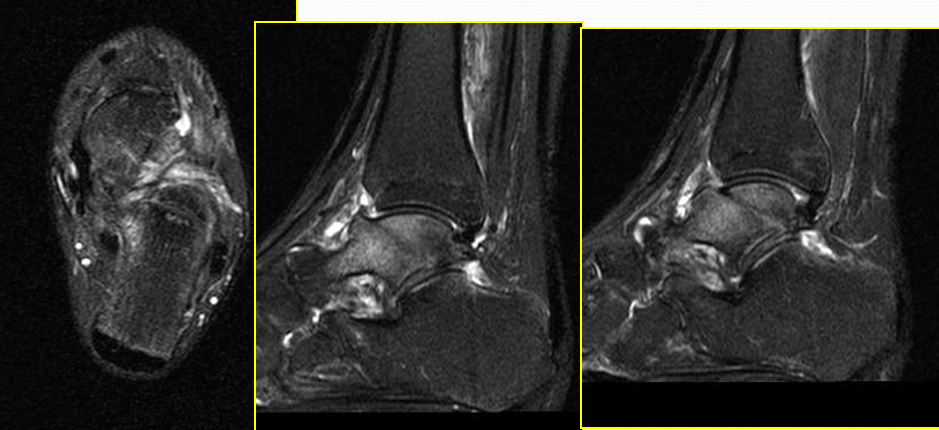

踝关节韧带损伤MR表现

直接征象

韧带形态学上改变:韧带走行、宽厚度异常;韧带边缘不光整;韧带连续性部分或完全中断;韧带信号异常改变

辅助征象

韧带周围结构改变:脂肪间隙及关节腔异常变化;其他邻近组织或结构的异常改变,包括:骨、软骨损伤、肌腱损伤、关节腔积液等。